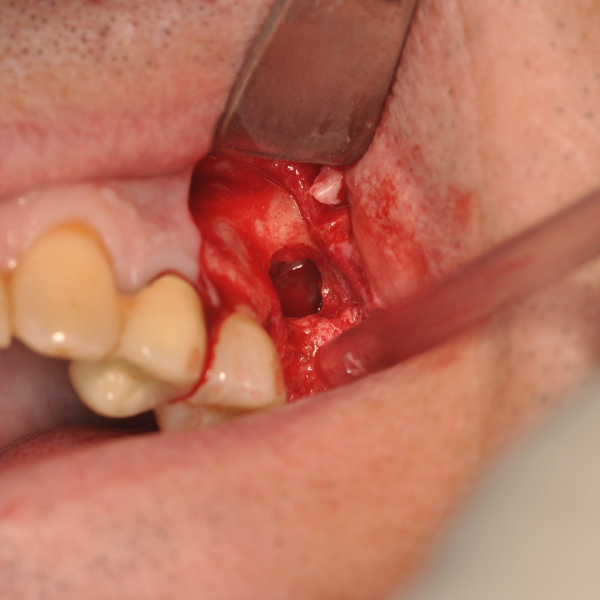

Removal Of Implant, Sinus Lift And Implant Replacement